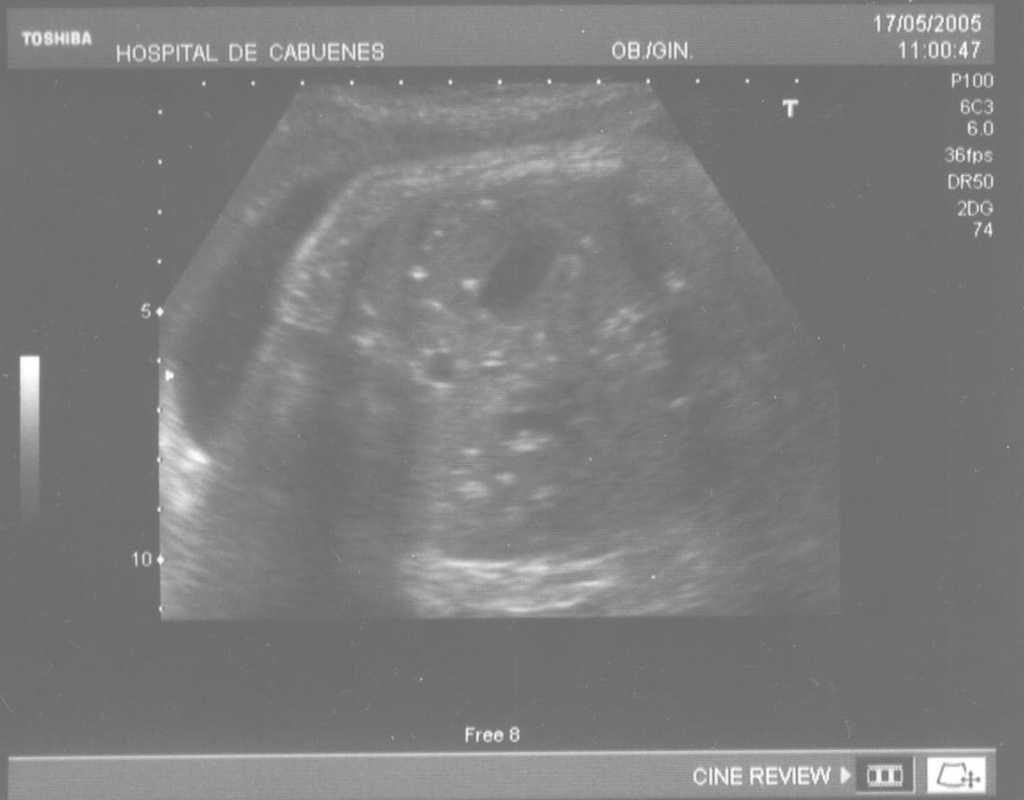

Las calcificaciones peritoneales son el hallazgo más consistente de PM y de hecho es la referencia en todas las series para establecer el diagnóstico posnatal en la radiografía simple de abdomen. Sin embargo, los criterios diagnósticos prenatales de PM no son uniformes y no se aplican de la misma manera por todos los autores. Las calcificaciones aparecen entre el 0-100% de los casos y en nuestra revisión, excluida la serie de Eckoldt et al8, en el 71,8%. Chan et al13 exigen como criterios para diagnóstico de PM la presencia de ascitis más dilatación de asas intestinales o calcificaciones. Sólo encuentran calcificaciones en 1/7 casos y argumentan que pueden pasar inadvertidas a los ultrasonidos. Eckoldt et al8, en una serie de 11 casos, no describen calcificaciones en ninguno y añaden: «no es común en nuestra institución practicar rayos X a la mujer gestante», e incluyen como diagnóstico prenatal de PM un caso con sólo ascitis, dos con ascitis e intestino ecogénico y dos con ascitis y polihidramnios, criterios que parecen insuficientes para establecer el diagnóstico de PM, aunque sea confirmado posnatalmente. Kamata et al23 sólo encuentran calcificaciones en 5/20 casos. Otros casos aislados comunicados tampoco encuentran calcificaciones1,10. El estudio de Dirkes et al14, citado en todas las comunicaciones por su clasificación de la PM en función del probable pronóstico neonatal, comunica calcificaciones en 9/9 casos y manifiestan: «el más frecuente y consistente hallazgo ecográfico, que es virtualmente patognomónico de PM, es la presencia de calcificaciones intraabdominales descartando su origen biliar, vascular, intraluminal, de órgano sólido o calcificación tumoral (...) la ascitis fetal aislada, la dilatación intestinal o el polihidramnios no son suficientes para el diagnóstico de PM». Chalubiski et al5 encuentran calcificaciones en algún momento del seguimiento prenatal en 8/9 casos y lo consideran el hallazgo más frecuente; Shyu et al12, en 16/17 casos; Tseng et al24, en 15/19 casos, y Foster et al4, en 6/7 casos y revisan los 19 casos comunicados previamente de diagnóstico prenatal de PM y encuentran calcificaciones o masas ecogénicas en 16/19 casos. Estroff et al6 comunican calcificaciones en 3/3 casos; éstas también están presentes en numerosos casos aislados1,3,7,25-27. Conviene tener presente que las calcificaciones abdominales encontradas en la PM son de localización peritoneal (extendidas por la superficie peritoneal) y deben distinguirse de las calcificaciones parenquimatosas, limitadas al parénquima hepático y, menos frecuentemente, al esplénico28. Aunque las calcificaciones peritoneales suelen ser más difusas, más numerosas y más groseras (como el caso que describimos; fig. 1) no debe obviarse este diagnóstico diferencial, de mayor importancia cuando la calcificación es el único hallazgo y de mayor dificultad cuando son escasas o se asocian con polihidramnios, pues en estas ocasiones no debemos pasar por alto la posibilidad de infección fetal u otras etiologías29. Además, debido al gran tamaño del hígado fetal, en ocasiones puede ser difícil localizar con precisión si las calcificaciones son peritoneales o hepáticas30. Sugieren una localización peritoneal: a) las calcificaciones que respetan el parénquima hepático y esplénico y se localizan en sus márgenes; b) la formación de láminas que «perfilan» el diafragma, y c) la localización en el escroto de un feto varón, que son particularmente diagnósticas de PM, debido a la conexión del saco escrotal con la cavidad peritoneal a través del proceso vaginal. Estos hallazgos estuvieron presentes en el caso que describimos (figs. 2, 3 y 4). Más raramente se localizan en el tórax por comunicación a través de los hiatos de la cava, la aorta o el esófago31. Debe tenerse presente la localización escrotal para establecer el seguimiento, pues no es inusual que en los primeros meses neonatales den lugar a masas o un escroto agudo que requieren intervención quirúrgica; la dificultad para orientar el diagnóstico es mayor cuando falta el antecedente de PM prenatal32-38.

Figura 1. Calcificaciones peritoneales difusas.